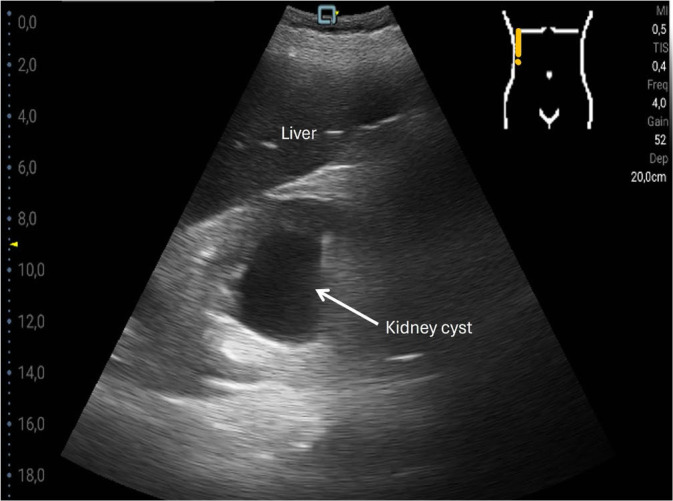

Results: The most common pathological findings were renal cysts in 34/120 (28.3%), left-sided or right-sided pleural effusions in 33/120 (27.5%) and 29/120 (24.2%) patients, respectively, dilatation of the vena cava in 24/120 (20.0%), and urinary retention in 14/120 (11.7%) patients. In 13/120 (10.8%) patients, the sonographic examination resulted in a diagnostic consequence, while in 38/120 (31.7%) patients in a therapeutic consequence. Among the false-negative findings using the hand-held ultrasound device, no finding was of therapeutic relevance. Four findings that were missed by the hand-held ultrasound device were diagnostically significant: two lesions of the kidney, one lesion of the liver, and one case of urinary stasis kidney.

Abstract Image